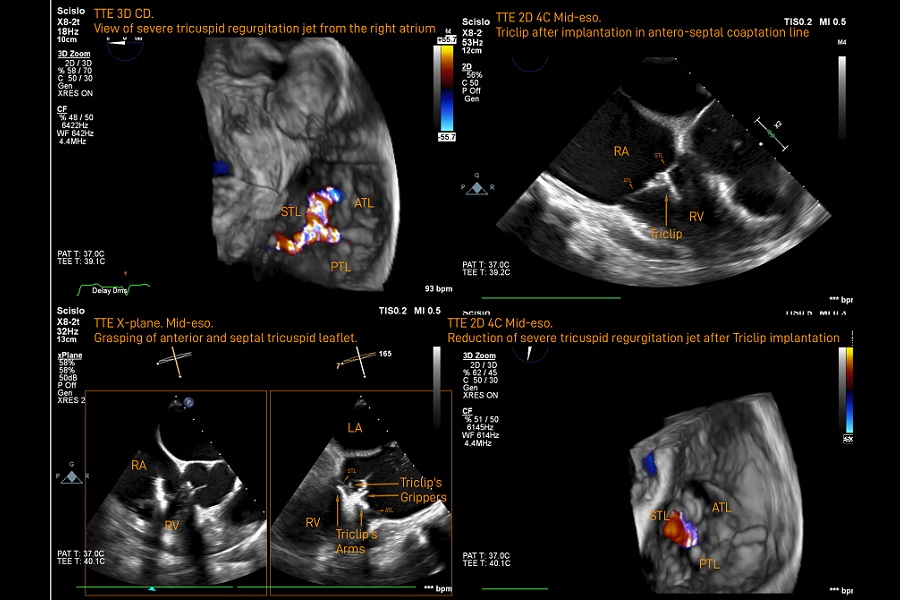

W dniu 28 kwietnia 2021 wykonano pierwszą w Polsce przezcewnikową naprawę izolowanej niedomykalności trójdzielnej metodą brzeg-do-brzegu za pomocą dedykowanego systemu Triclip (Abbott). Zabieg przeprowadził zespół w składzie operatorzy: dr n. med. Adam Rdzanek, dr n. med. Arkadiusz Pietrasik, echo-nawigatorzy dr n. med. Piotr Scisło, dr hab. n. med. Agnieszka Kapłon-Cieślicka, anestezjolog dr Dorota Komorowska, piel. Renata Makowska, piel. Grażyna Drozdowska przy pomocy proktorów Paolo Romitelli’ego, Tanami Nechemya i Daniela Marciniaka (Abbott), opieka kliniczna nad chorym tech. Sławomir Dziewulski i dr n. med. Ewa Pędzich-Placha.

Zabieg został wykonany w Oddziale Klinicznym Kardiologii Inwazyjnej (Kierownik: prof. dr hab. n. med. Janusz Kochman) Kliniki Kardiologii (Kierownik: prof. dr hab. n. med. Grzegorz Opolski).

Zabiegi korekcji niedomykalności trójdzielnej wykonywane są w Klinice od 2018 roku, jednak dotychczas mogły być one przeprowadzane jedynie w czasie zabiegu na zastawce mitralnej.